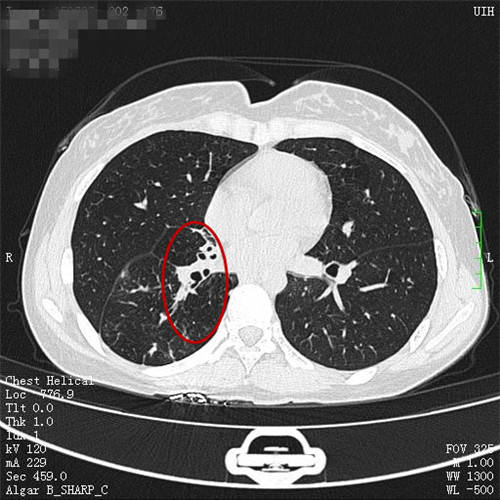

谭建龙副主任医师在接诊后通过详细的病史询问和体格检查,认为王女士很可能有肺结核合并气管支气管结核,立即进一步安排胸部CT检查和支气管镜检查,胸部CT检查发现其的右侧中间段支气管闭塞,右肺有2/3的肺被完全阻塞,支气管镜检查也发现右中间段支气管被大量的坏死物堵塞,多处气管都被病变累及,若不积极治疗,病变可能累及双肺,给病人造成不可挽救的伤害。